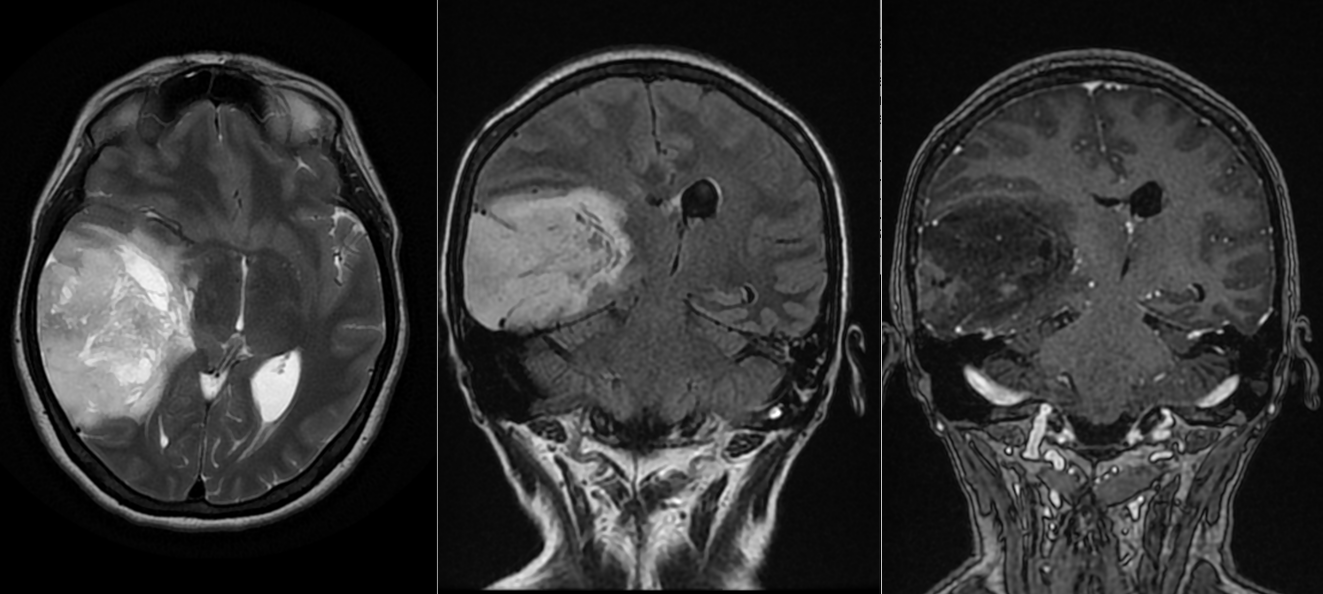

Astrocitom anaplazic parietal drept

Astrocitom anaplazic grad III temporo-occipital drept – fără recidivă la 8 ani dupa operație

Astrocitom grad III operat – progresie sub tratament